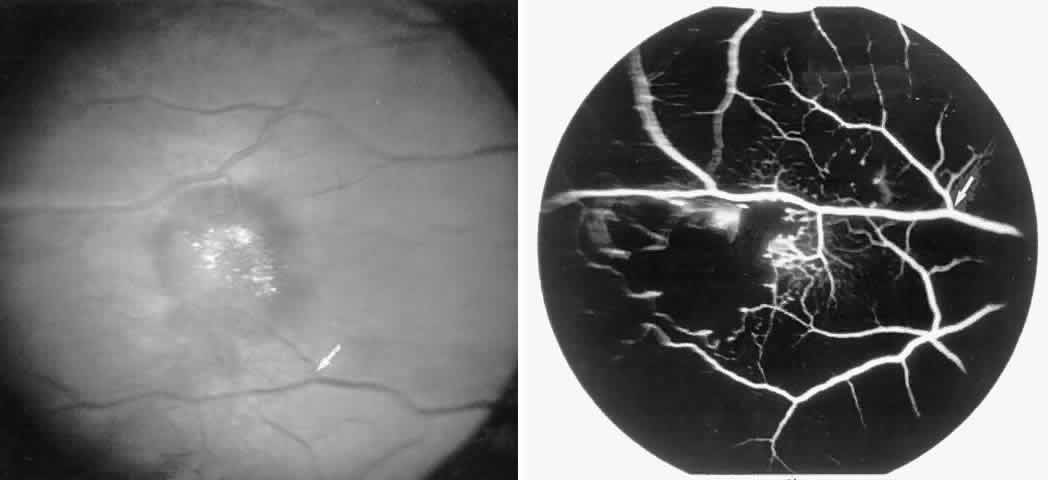

Occlusions of the fine vasculature of the macular and perimacular area have been reported in 10% to 40% of patients with sickle cell disease.18,83,91–99 In the acute phase, the occluded vessel will have a dark red appearance and may appear as a dark line on fluorescein angiography (Fig. 9). Nerve fiber layer infarcts (cotton-wool spots) are seen (see Fig. 8D and E;Fig. 10).100

Fig. 9. A 27-year-old man with homozygous sickle cell anemia. A. Fluorescein angiogram of the right eye shows multiple arteriolar occlusions temporal to the fovea (arrows). B. Same area 6 months later shows more extensive occlusions. The black arrowheads (A and B) identify corresponding arteriolar bifurcation.

Fig. 10. A 33-year-old woman with SC disease and stage III sickle cell retinopathy. A. Photograph of the right eye shows a cotton-wool spot with a dark segment identifying the occluded vessel (arrow). B. Fluorescein angiogram demonstrates nonfilling of the occluded vessel (arrow). C. Eighteen months later, the occluded vessel is still visible (arrow). D. Fluorescein angiogram demonstrates that there is still nonfilling of the vessel (arrow).